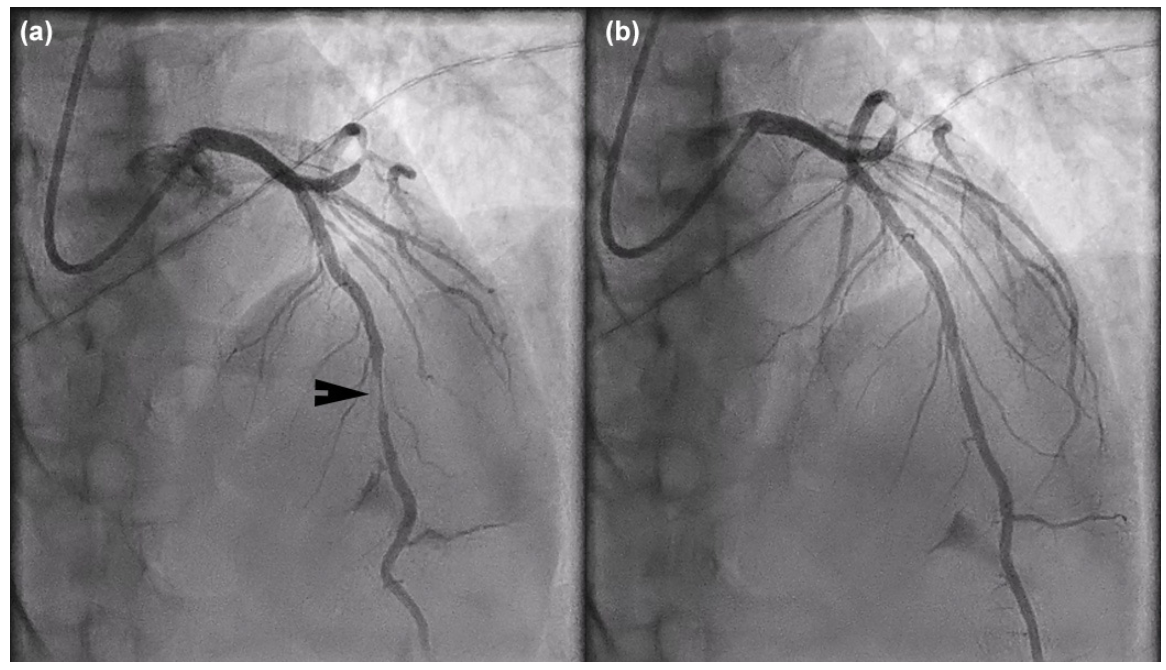

A 63-year-old male with a history significant for 50 pack years of tobacco use and a cerebrovascular accident presented with unstable angina. His electrocardiogram (ECG) showed sinus bradycardia with nonspecific ST/T wave changes (Figure 1A). Coronary angiography demonstrated significant myocardial bridging of the mid left anterior descending artery (LAD) (Video 1 and Figure 2) and nonobstructive coronary artery disease (CAD) otherwise. His left circumflex (LCX) CAD was physiologically insignificant on assessment with instantaneous wave-free ratio (Figure 3). The following day, the patient developed transient anterior ST-segment elevation myocardial infarction with a troponin of 0.5 ng/mL (Figure 1B). He was brought back for coronary angiography with intracoronary imaging. His baseline angiogram was unchanged and optical coherence tomography (OCT) was performed in the LAD, which showed evidence of acute plaque rupture within the myocardial bridging segment (Video 2 and Figure 4). There was a concern for stenting the bridging segment due to reported higher rates of target-lesion revascularization and concerns of stent thrombosis, stent fracture, and coronary perforation. Therefore, cardiothoracic surgery was consulted for unroofing of the mid LAD or surgical bypass, which are generally considered safe and effective.1,2 The left internal mammary artery was found to be a poor conduit in the operating room due to size and flow limitation. Given that the patient already had a median sternotomy, surgical revascularization with saphenous vein grafting and surgical myotomy to relieve the systolic compression were performed. The latter would facilitate durable percutaneous revascularization options in the future.